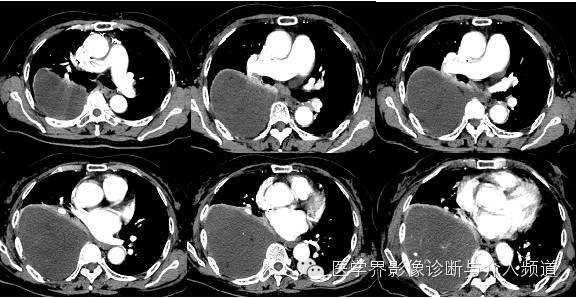

【影像图像】

【影像学表现】

右侧胸腔内见巨大囊性占位,内夹杂少许小片状脂肪及点状钙化灶。内可见分隔。增强动脉期内见血管影走形,静脉期可见病变轻度强化,CT值约为30 Hu,内分隔强化明显。